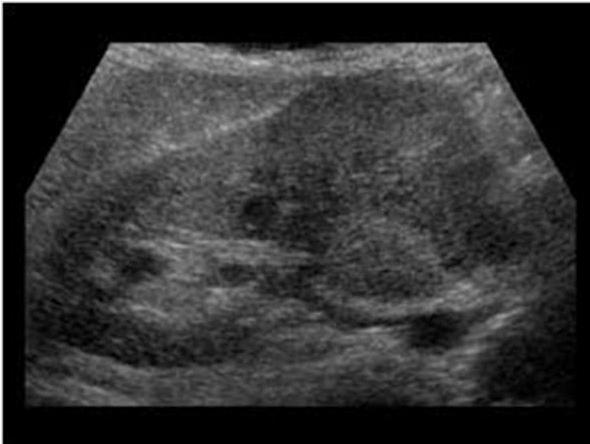

Xanthogranulomatous Pyelonephritis XGPN

Chronic Pyelonephritis due to stone

type of Chronic Pyelonephritis

Xanthogranulomatous Pyelonephritis XGPN

Chronic Pyelonephritis due to stone